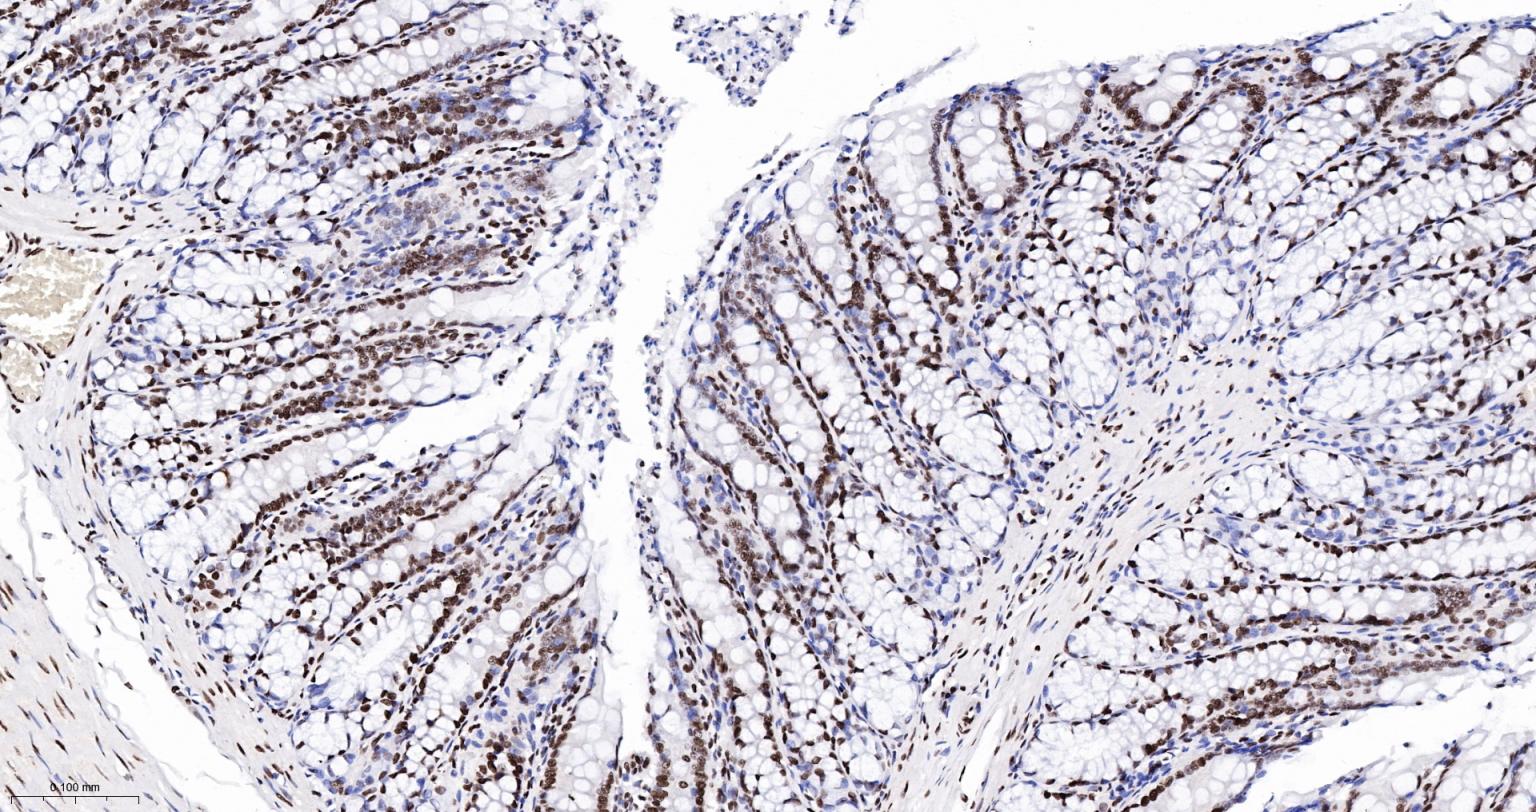

Paraformaldehyde-fixed, paraffin embedded Human Colon; Antigen retrieval by boiling in sodium citrate buffer (pH6.0) for 15 min; The section was incubated with SFPQ Monoclonal Antibody, Unconjugated (bsm-61746R) at 1:200 overnight at 4°C, followed by conjugation to the bs-0295G-HRP and DAB (C-0010) staining.